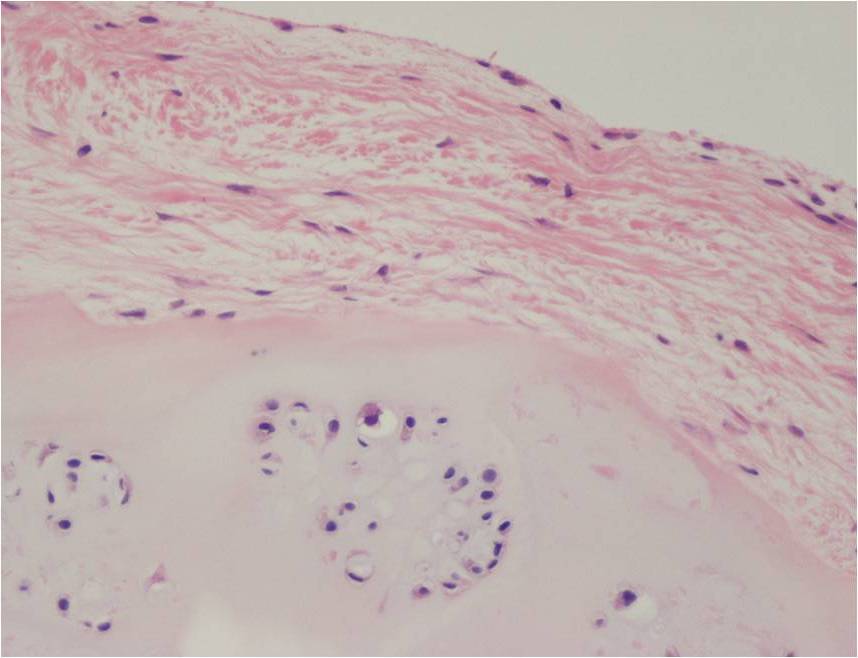

Synovial chondromatosis is an uncommon, benign, process that occurs in large joints, such as the knee (50%), hip, elbow, or shoulder. This process mainly affects synovium and hence most commonly arises from joints and tendons which are lined by synovium. Synovial Chondromatosis may also affect bursae and extend into surrounding soft tissues. This condition is seen in patients between 20 and 50 years of age and most commonly in men (male-female ratio of 2-4/1). The patient usually complains of pain, stiffness, crepitance, swelling, and joint locking. The knee is the most common site to be affected. Symptoms are long-standing and progressive. The plain x-ray may be normal (5 to 33%) or there may be small flecks of calcification (Fig. 1 & 2). On MRI the nodules of cartilage are easily seen. MR imaging may also show synovial thickening, joint erosions and intraarticular calcifications. The signal characteristics of these intraarticular bodies depend of their composition. If mineralization is not present the signal intensity follows the cartilage signal with intermediate signal on T1 images and high signal on T2 weighted MR images. Uniformly calcified bodies follows bone density on all sequences with bone marrow signal centrally and low signal peripherally (Fig. 3-5). Histologically the cartilage is arranged in nodules, which are quite cellular (Fig. 7-9). Synovial lining is present surrounding the cartilage nodules (Fig. 8). The cartilage nodules are often referred to as loose bodies however they are not really loose and embedded in the synovium lining. This is considered a metaplastic condition as opposed to a true neoplastic condition. Rarely it may turn into a malignancy usually a low grade chondrosarcoma. Malignant change is suggested by deep erosions into adjacent bone.

Fig. 7 – 9. Microscopic Pathology. Low (Fig. 7) and intermediate (Fig. 8 & 9) magnification demonstrates nodules of cartilage with high cellularity. Synovial lining is present surrounding the cartilage nodules.